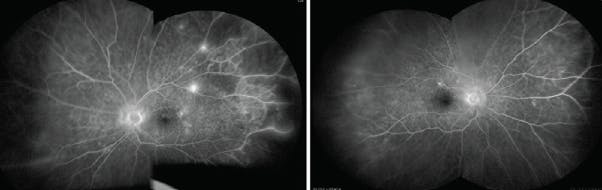

<p>Figure 3. OCT showed trace macular edema in each eye.</p>

Figure 3. OCT showed trace macular edema in each eye.

Examination revealed UCVA of 20/25 OD and 20/15 OS, normal IOPs, and well-centered IOLs. Dilated fundus examination revealed asteroid hyalosis in the right eye, clear vitreous in the left eye, and healthy nerves with a cup-to-disc ratio of 0.3 in each eye. Both eyes had prominent arteriovenous nicking changes, diffuse dot-blot hemorrhages in all peripheral quadrants, mild venous engorgement, and neovascularization along the superior and inferior temporal arcades. Rare macular dot-blot hemorrhages were appreciated (Figure 1). Fluorescein angiography revealed delayed arteriovenous filling time, peripheral nonperfusion, several areas of neovascularization leakage, and leaking microaneurysms in the macula (Figure 2). OCT revealed trace macular edema (Figure 3).